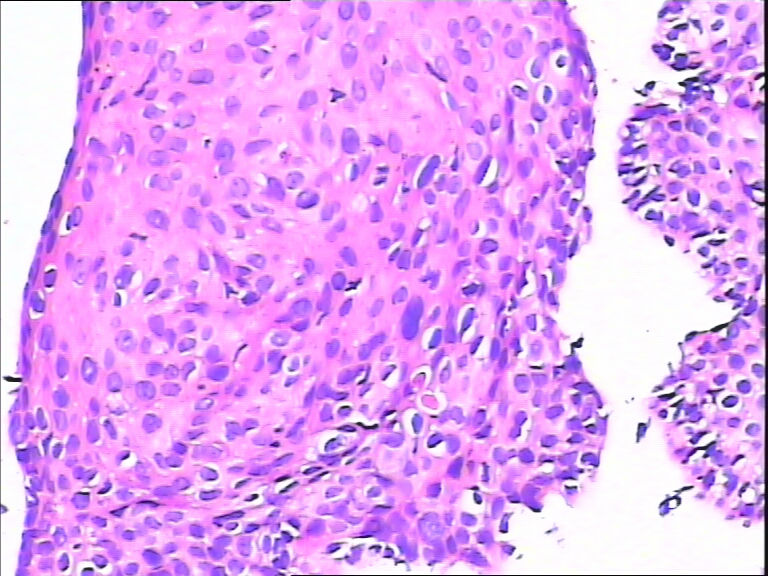

45y,触血,宫颈多点活检。

不同级别的CIN,局灶已达到CIN3。

HPV感染。局部已达到CIN2-3

HPV感染。灶性CIN2-3